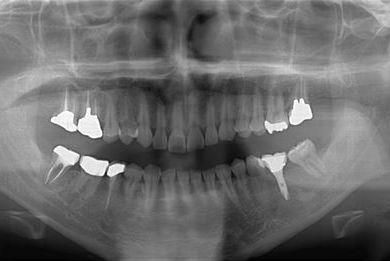

インプラントの症例写真 IMPLANT

インプラント治療+セラミック治療

| 性別/年齢 | 男性 / 32歳 | ||||||||||||||||||||||||||||||||

| 主訴 | 何ヵ所か虫歯が進行してしまったので治療をして欲しい。以前抜歯をした所についてはインプラントを希望する。 | ||||||||||||||||||||||||||||||||

| 治療内容 | インプラント1本、ハイブリッドセラミック4本、ハイブリッドセラミックインレー1本、歯肉歯槽骨整形 | ||||||||||||||||||||||||||||||||

| 総治療費 | 756,525円 | ||||||||||||||||||||||||||||||||

| 治療期間 | 8ヶ月 |